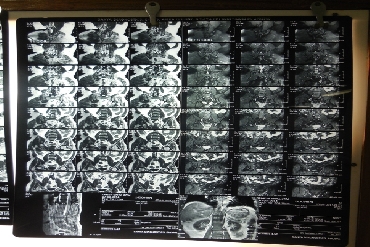

A herniated lumbar disc can push on spinal nerves and cause severe, shooting leg pain, numbness and/or weakness. A percutaneous disc removal (PDR) can remove a portion of the herniated disc that is compressing spinal nerves through a small incision in the skin. This minimally invasive approach uses a much smaller incision than traditional open spinal surgeries and avoids damage to the low back muscles.

In some cases, removing part of the herniated disc in a partial discectomy procedure can also prevent the disc from irritating the nerve.